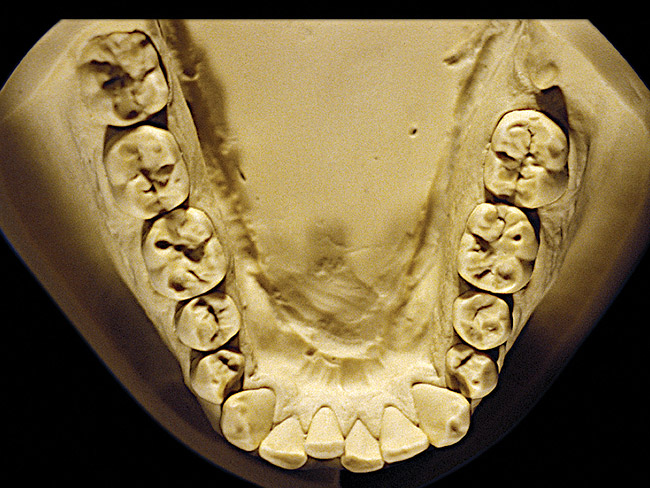

Figure 2  Advanced NCLTS from bruxism, mandibular arch.

Figure 2

The patient shown in Figure 3 and Figure 4 exhibited severe NCLTS from bruxism. Examination of the casts indicated that the NCLTS was progressively greater toward the anterior teeth. Cupping and cratering was not present because there was no secondary cause. Figure 5 and Figure 6 detail another bruxism patient, but to a lesser degree and one with cupping/cratering caused by toothpaste. The cups or craters were not caused from bruxism because the teeth could not touch the bottom of the invaginations. In both featured patients, upon hand-articulating the casts, the NCLTS facets matched up and the diagnosis of bruxism was confirmed.